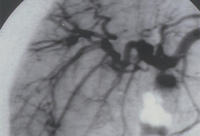

Angiografia renal mostrando aneurismas, uma característica clássica de poliarterite nodosa (PAN)

Do acervo do Dr Raashid Luqmani